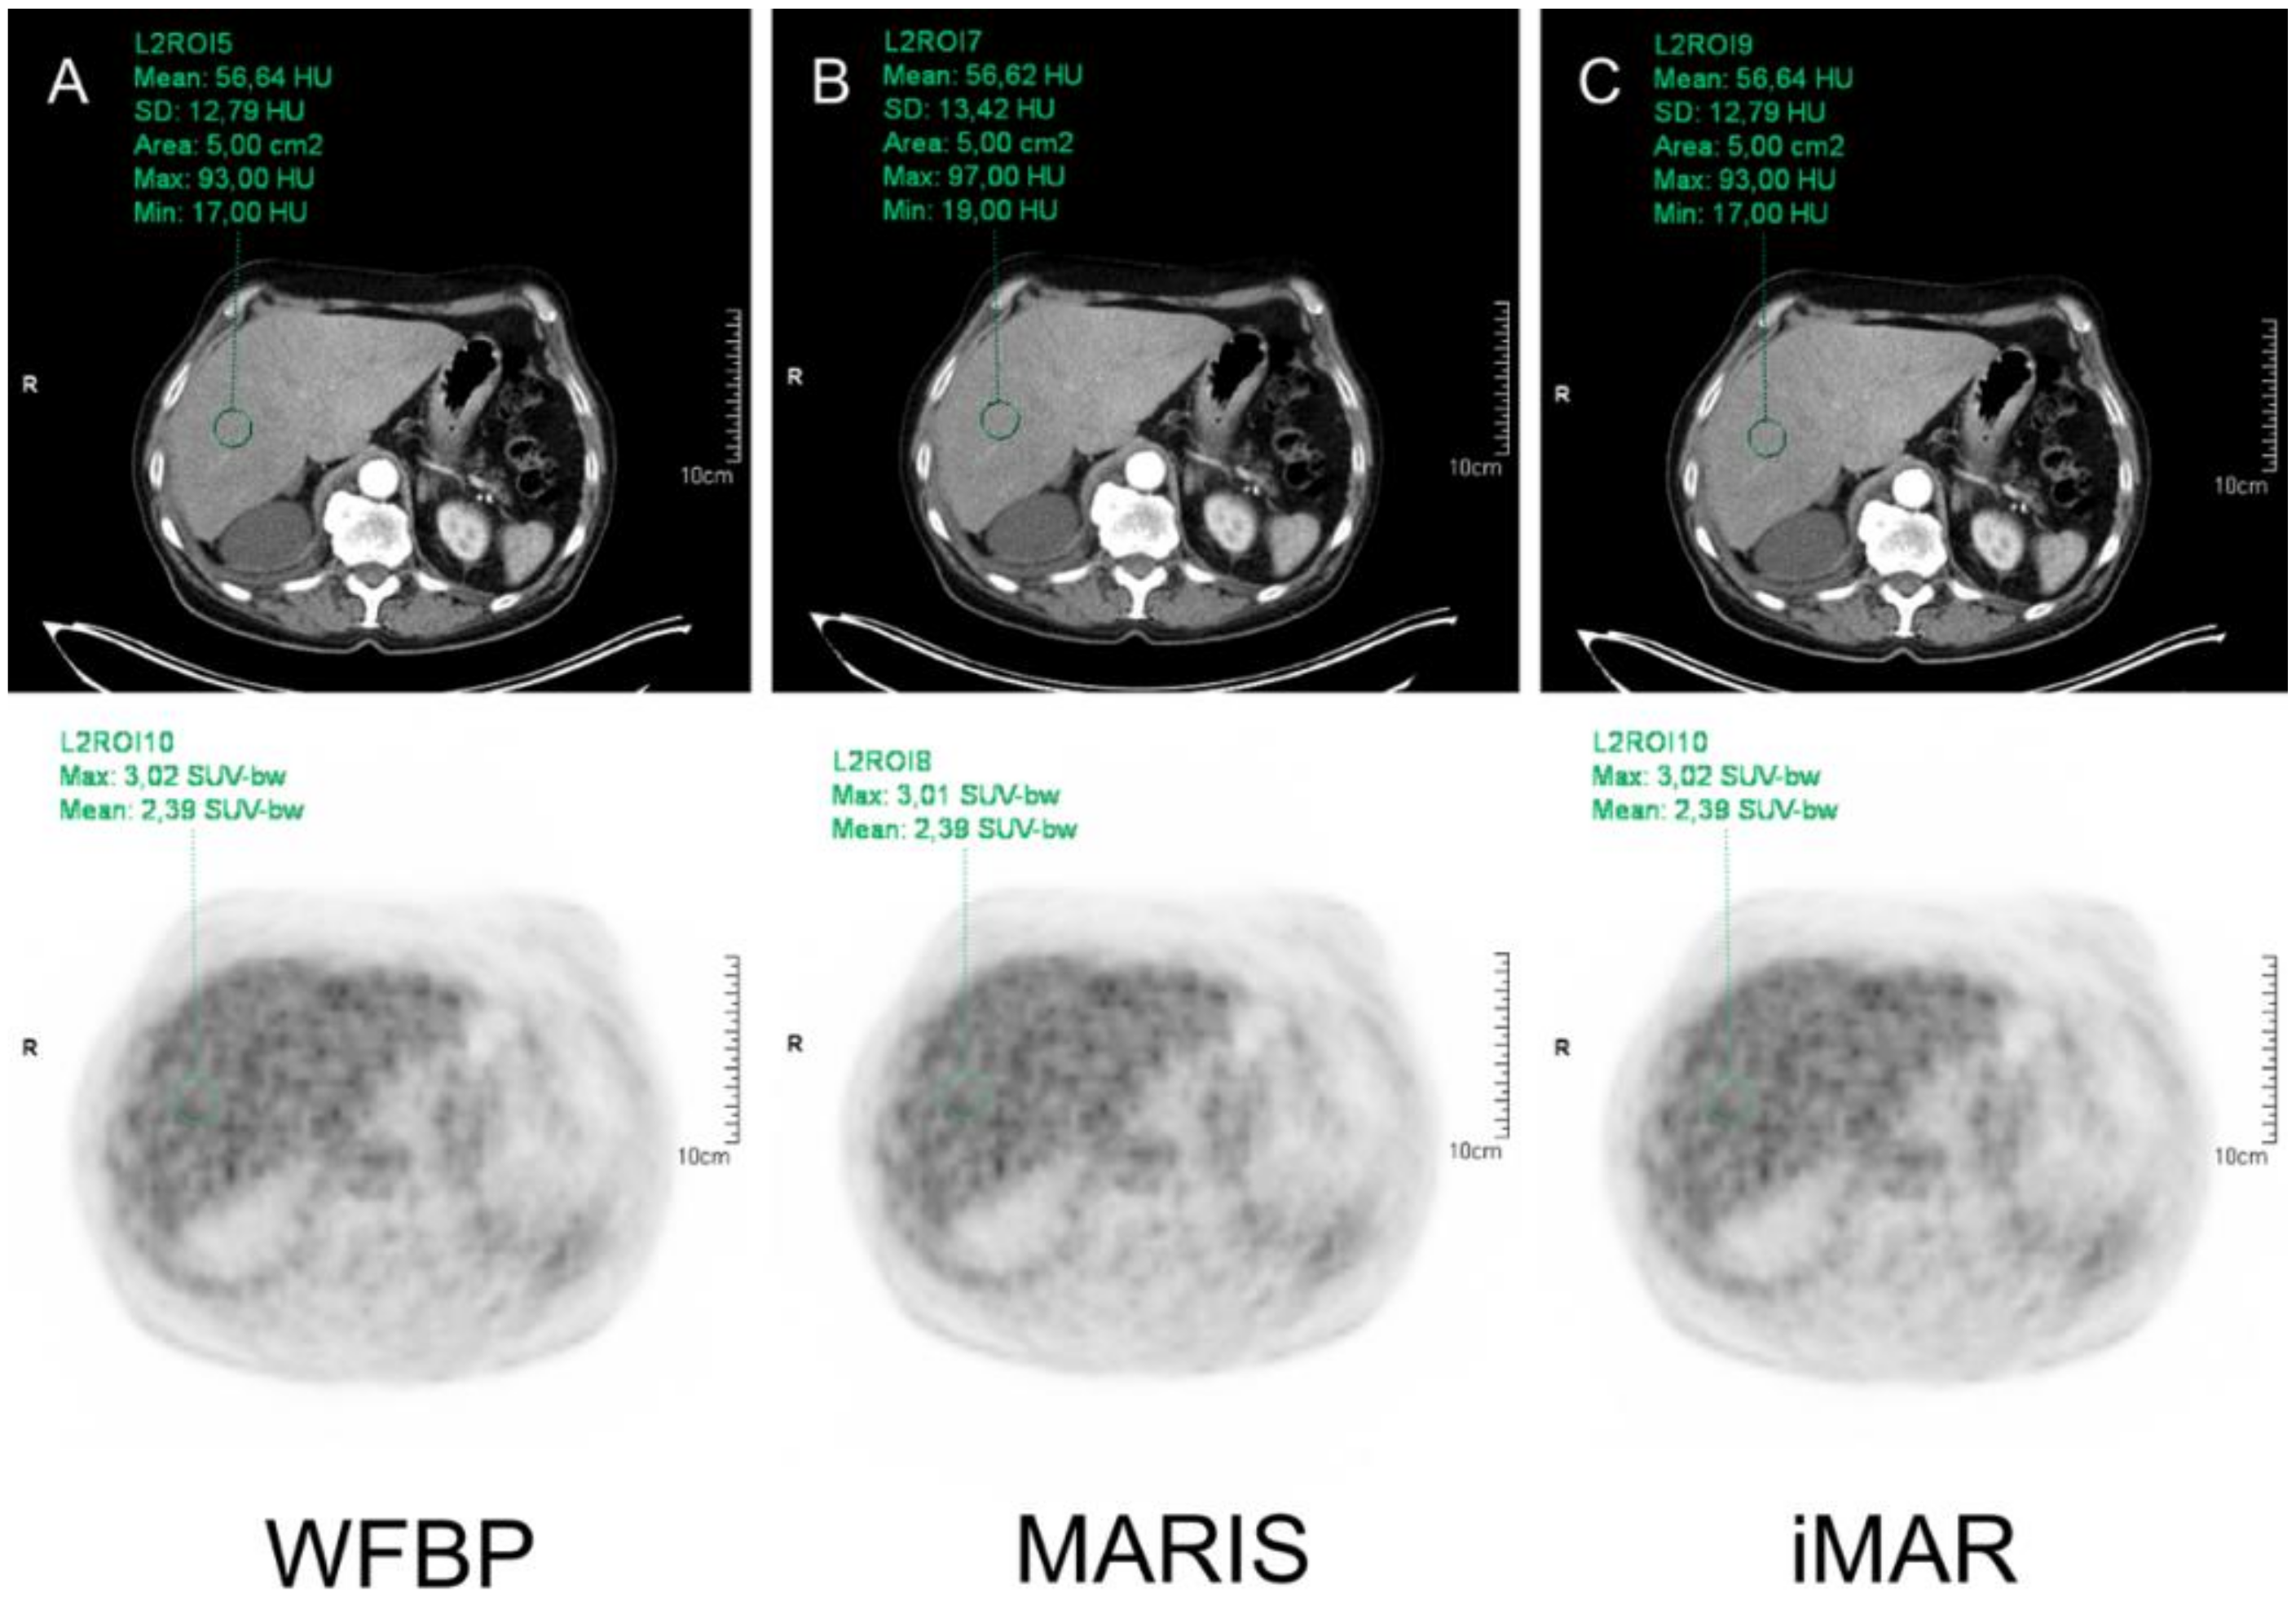

2.3. CT Image Reconstruction

2.4. PET Reconstruction

2.5. Image Analysis

3.2. HU Measurements

3.3. SUV Measurements